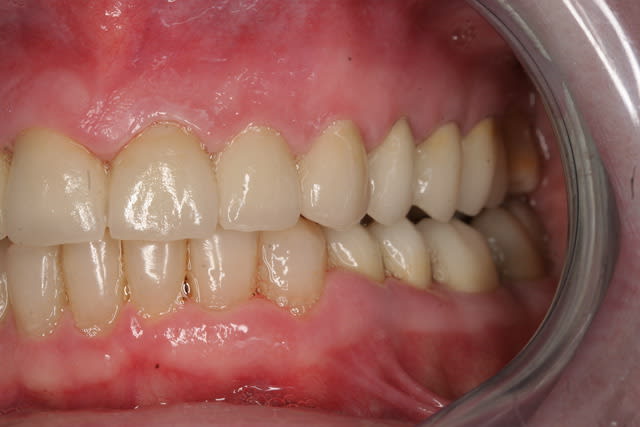

Donc la suite, évidement ortho: ingression du bloc incisivo canin sup avec ré alignement des arcades, extraction de la 14 nécessaire et ré alignement des milieux interincisif.

Pendant la finalisation du haut (axe mésio-disto incisif, à corriger à la fin pour faciliter gingivoplastie incisif sup). Il y a eu composite vestibulaire pelliculaire sous digue de 33 à 43, reprise soins et ancrage + provisoires 34,35, 36, 46; et composite sous digue 37 et 47.

Photos après dépose du haut. Comme dit dans précédent post, le bas avait été déposé quelques semaines auparavant et préparé entre temps, d'où contention, composites et provisoires déjà en place.